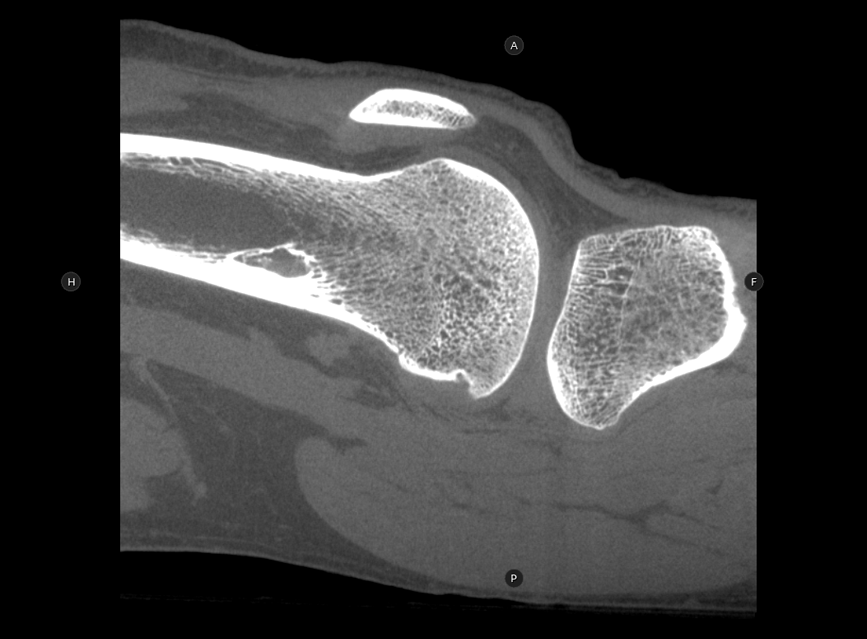

HRCT

High Resolution Computed Tomography. Outstanding image quality with a voxel size up to 100 µm